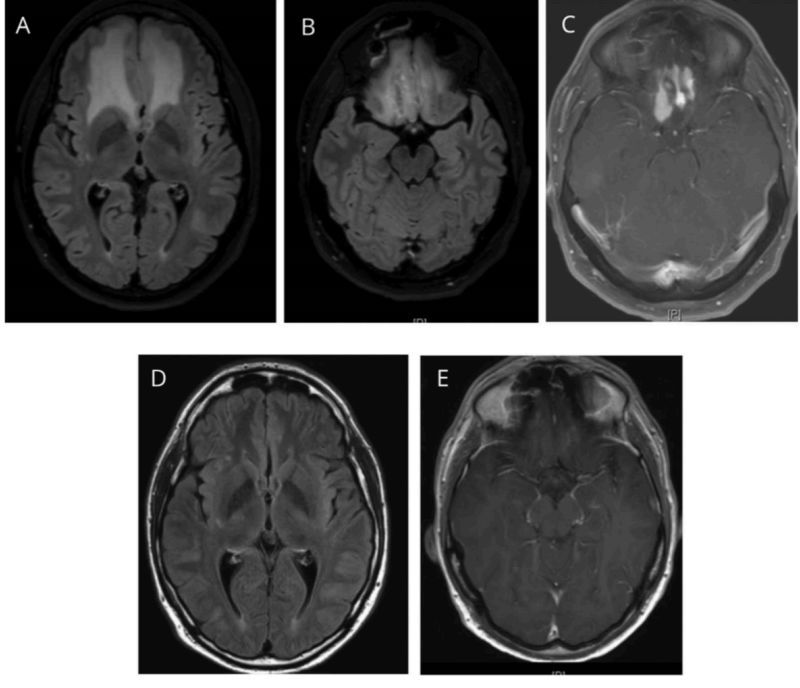

一位70岁的女性在12周内表现为进行性记忆障碍、穿衣困难、尿*禁失**和步态共济失调。检查显示全身性双侧对称性齿轮样肌张力增高,步态共济失调,无肢体辨距不良,下颌反射增强,嗜睡。上肢可见不连续的、多灶的、远端优势的肌阵挛,活动增强,对触摸或惊吓不敏感。简易精神状态检查(MMSE)评分为6/27。

诊断: 硬脑膜动静脉瘘(DAVF)

脑磁共振成像显示双侧大脑半球对称、 融合的T2高强度(图a)。梯度回波图像(图b)显示双侧小脑裂和脑沟的显著静脉(低强度,曲线信号;黄色箭头)。未发现实质性血肿或静脉窦血栓形成。脑CT显示弥漫性脑水肿,脑沟消失,额角受压。

术后CT扫描显示额角正常,外侧裂开放,皮质沟(d)显示良好。

硬脑膜动静脉瘘(DAVF)在脑血管造影上得到证实。在上矢状窦、右横窦、皮质浅静脉和深静脉系统可见明显的静脉窦逆行引流。

病人行栓塞术后认知功能改善(6~14/27),嗜睡和肌阵挛完全消失。

DAVF患者的痴呆可归因于静脉高压,导致白质改变和静脉高压性脑病。